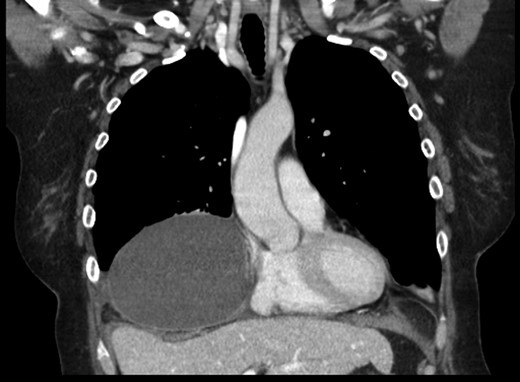

A 69-year-old female was referred to our clinic for an incidental finding of a large Morgagni hernia found on a recent CT chest scan for lung cancer screening. Patient reported occasional shortness of breath after prolonged ambulation but denied chest pain. She did have remote history of acid reflux symptoms but nothing recently. She denied issues with prematurity or issues with development as an infant, chest trauma, or MVA history. She did complain of occasional right shoulder pain but attributed this to arthritis. Denied history of heart attack, stroke, DVT, or PE. She had a 30-pack-year smoking history but quit a year prior. She was up-to-date on her colonoscopy, current within the past year. She denied hematochezia and melena, bowel habit changes or major body weight changes as well as any current abdominal pain. On examination her vitals were within normal parameters. Heart and lungs were unremarkable. Abdominal examination was soft with normal bowel sounds and nontender. Remainder of examination was unremarkable. Laboratory values included a normal CBC and BMP. A CT chest scan had demonstrated a large retroxyphoid hernia of Morgagni involving several loops of small bowel and transverse colon located in the right inferior hemithorax (Figs 1 and 2). No evidence of acute incarceration or strangulation were noted. A detailed discussion was undertaken with the patient regarding her hernia and she was consented for a laparoscopic repair with mesh.

Preoperative CT scan of chest demonstrating the wide retroxyphoid defect in the diaphragm with herniated small bowel and colon into the right inferior hemithorax.

Another slice of the CT scan of the chest revealing the large size of this Morgagni hernia with multiple loops of small bowel and colon in the right inferior hemithorax.